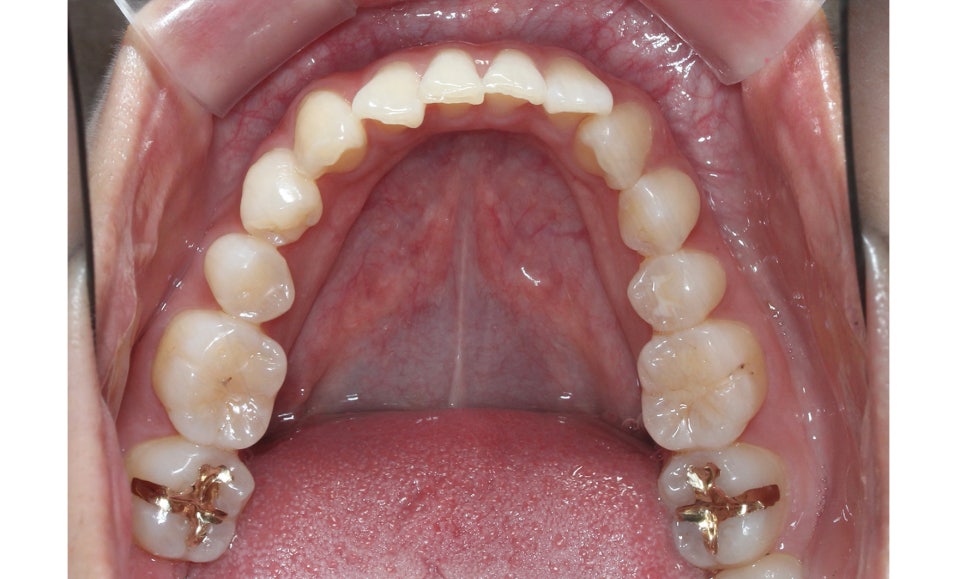

하악 또한 상악과 같이 전치부에서

발견되던 crowding이 사라졌고

치열이 가지런하게 바뀐 모습을 확인할 수 있는데요,

신논현치과에서는 위와 같은 부분적인

부정교합을 단기간에 심미적으로 교정할 수 있는

다양한 교정 방법을 연구하여 발전시키고 있습니다.

따라서 일반적으로 교정에 소요되는 시간보다

1~3개월 정도 단축하여 교정을 마무리하실 수 있는데요,

오늘 소개해드린 클리피씨교정의 경우 평균적인

교정기간이 1년 내외이기 때문에 빠른 교정을

원하시는 경우 적용이 가능합니다.